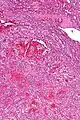

Intermed. mag. Very high mag.

Littoral cell angiomas show in CT scans. They are diagnosed by pathologists by taking a sample of the tumour via Fine Needle Aspiration or Core Needle Aspiration or from a splenectomy. Histologically, they have anastoming small vascular channels and cystic spaces with papillary projections.[2]